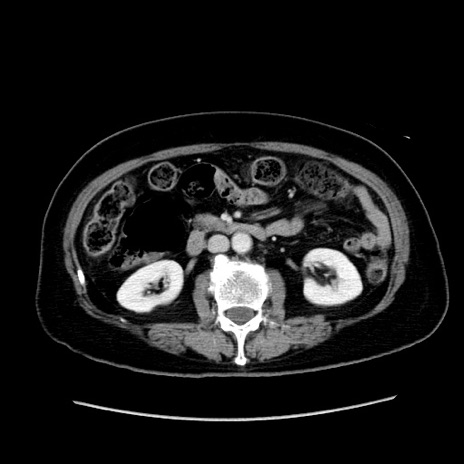

症例19(横断像)

【症例】80歳代女性

【主訴】下腹部痛

【現病歴】約8時間前より下腹部痛の出現あり、救急外来受診。

【既往歴】両側付属器切除

【身体所見】意識清明、下腹部正中に手術痕あり、その部位に一致して圧痛と反跳痛あり。腸蠕動音は亢進。

【データ】WBC 9300、CRP 0.15